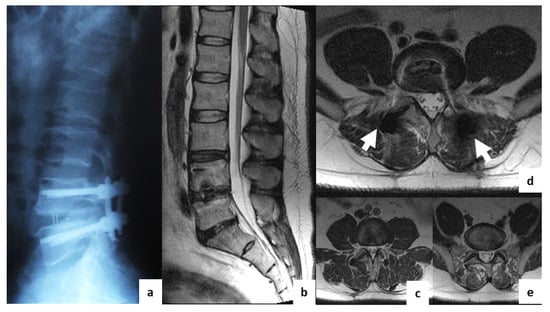

Comparison of MRI Visualization Following Minimally Invasive and Open TLIF: A Retrospective Single-Center Study

3. Results